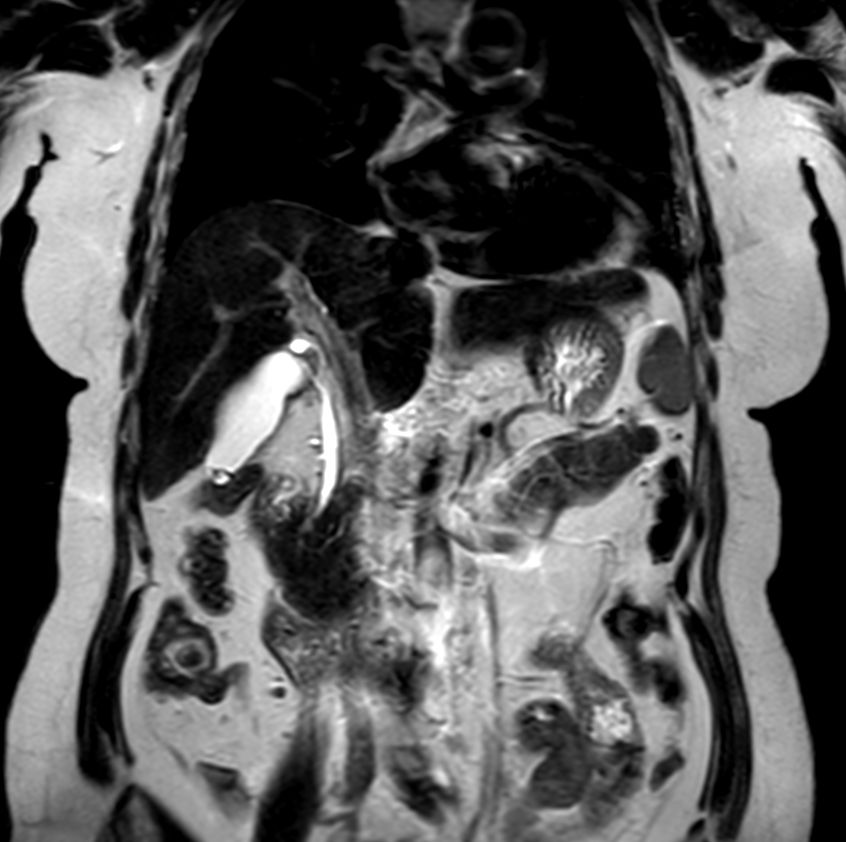

MR Elastography (SE-EPI, 4 slices)

MR Elastography (SE-EPI, 4 slices) (Stiffness Map)

MR Elastography (SE-EPI, 4 slices) (processing)

Liver ExamCard including single breath hold 3D mDIXON Quant for non-invasive liver fat quantification of the whole liver with high accuracy (± 3.5%) and reproducibility (± 1.4%)1. And MR Elastography for a non-invasive assessment of differences in tissue stiffness of the liver. Image processing is fully integrated at the scanner with automated calculation of Elastograms, reflecting tissue stiffness in kPa and statistical confidence map for reliability assessment.